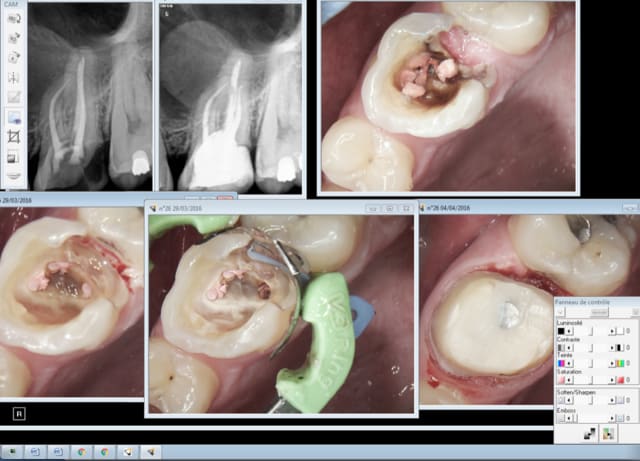

Capture d e cran 2016 04 12 08.20 - Eugenol